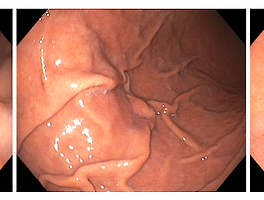

글리코겐 가시세포종(Glycogenic acanthosis)

이것은 전형적으로 정상 점막 위에 다양한 일정 크기의 둥근 모양의 융기를 나타내며 보통 식도의 중간 부위에 있습니다.

이것은 크기가 전형적으로 2 - 10 mm이지만 15 mm까지 큰 것도 있습니다.